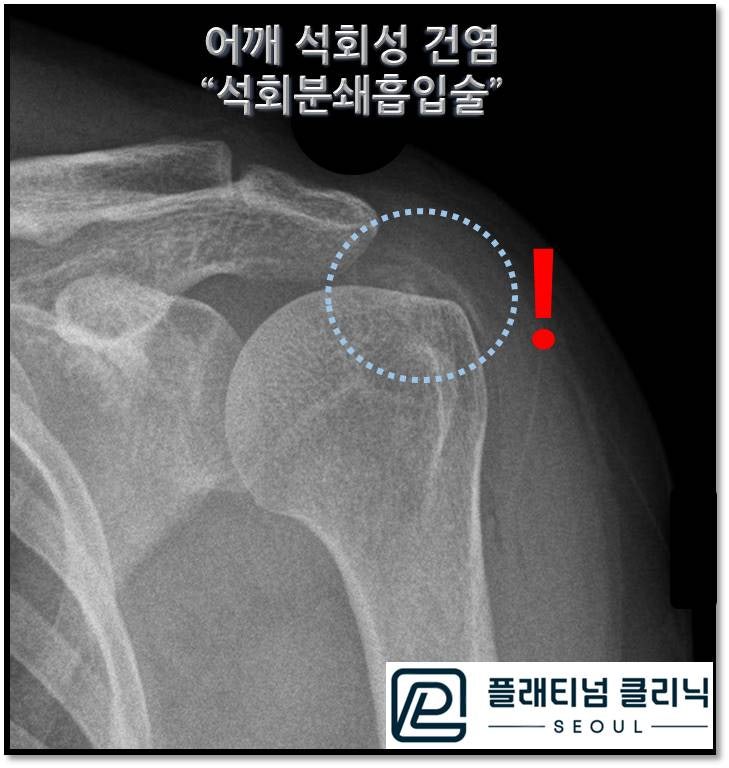

시술 직후 촬영한 X-ray 를 보면 이전에 하얗고 선명하게 보이던 석회가 거의 다 보이지 않습니다.

시술 전 후 X-ray 를 비교해서 보면 노란 점선으로 표시된 석회가 시술 후 거의 보이지 않습니다. 약간 남은 석회의 경우 자연스럽게 흡수되기도 하고 이를 더 빠르게 흡수 시키기 위해 체외충격파 치료를 추가적으로 할 수 있습니다. 또한 시술 당시 석회가 제거된 회전근개는 바람빠진 풍선처럼 속이 텅빈 상태가 되는데 이 부위가 다시 힘줄로 재생되는 것을 촉진시키기 위해 증식치료를 추가적으로 시행하였습니다. 환자분은 시술 이후 통증이 거짓말처럼 없어졌다면서 너무 좋아 하십니다. 석회성 건염의 근본적 치료는 석회를 제거하는 것입니다. 이것을 장기간 시간을 두고 체외충격파 치료를 해서 치료하는 것도 하나의 방법입니다. 하지만 석회의 양상에 따라 체외충격파 치료가 효과가 없는 경우도 있습니다. 석회성 건염의 통증이 어느정도인지 알기에 최대한 빠르게 그리고 효율적으로 치료하는 것이 최선이라고 생각합니다.